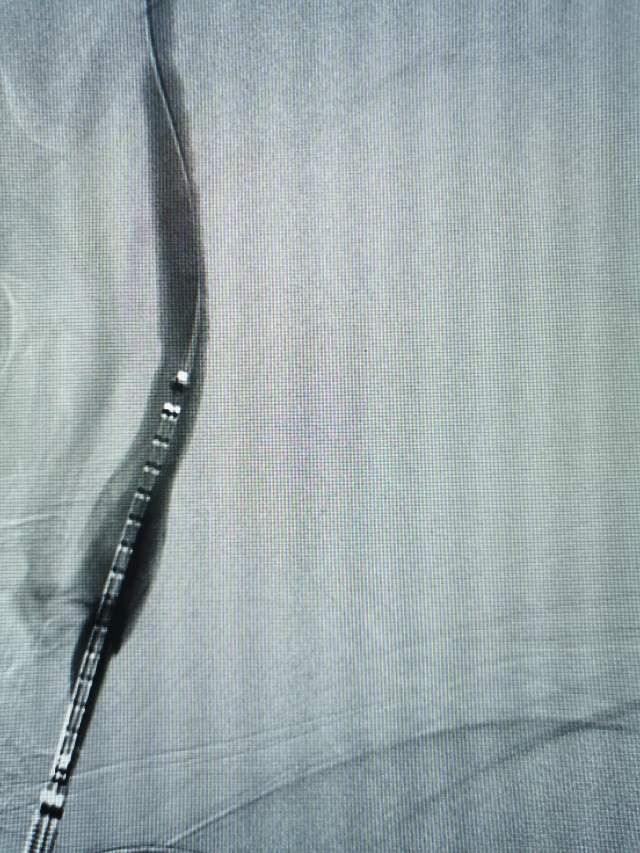

术后,紊乱的血流变得圆滑自然,血流快速丝滑通过左侧颈内动脉起始部,单位时间通过单位横截面的有效血流量增加,有利于改善低灌注,也有效防止了泥沙样栓子脱落。